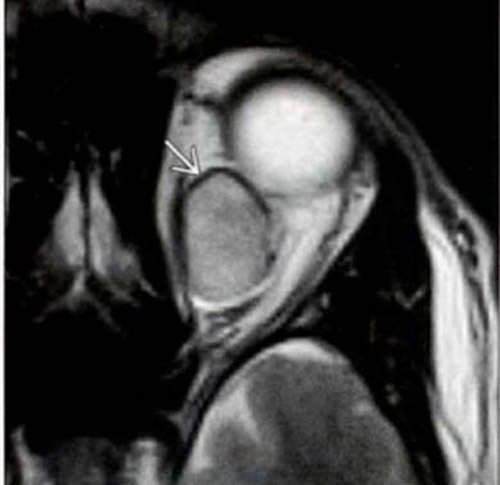

El diagnóstico es clínico y se complementa con técnicas de imagen. En la TC y la RM se observa proptosis, engrosamiento difuso de la musculatura extraocular y un característico aumento de calibre de la vena oftálmica superior (

Figura 7).

Figura 7. Fístula dural. A) imagen clínica con marcada congestión orbitaria, quémosis y limitación de los movimientos oculares. B) RM orbitaria en plano axial de fístula carótido-cavernosa izquierda. Secuencia T1SE en la que se aprecia un engrosamiento y ocupación del seno cavernoso izquierdo, con imágenes de vacío de señal en su interior (*). Asimismo se aprecia una estructura vascular patológica que se dirige a la órbita homolateral (<). Es evidente una marcada proptosis ocular y engrosamiento difuso de la musculatura extraocular del lado izquierdo.